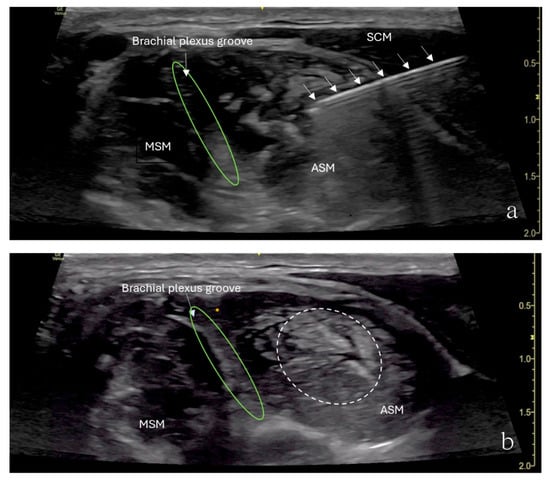

The patient underwent ultrasound-guided ASMB under minimal sedation. A high-frequency linear ultrasound probe was used to identify the anterior scalene muscle and adjacent neurovascular structures. After sterile preparation, a 24-gauge, 40 mm Sono-TAP needle (PAJUNK®, Geisingen, Baden-Württemberg, Germany), using an in-plane approach, was advanced from the anterior aspect of the neck posteriorly and inserted into the middle of the anterior scalene muscle (Figure 2). After negative aspiration, 5 mL of 0.5% ropivacaine was injected incrementally (Figure 2). The block provided immediate pain relief, and there was no numbness in the right upper extremity when the arm was elevated or abducted. However, the patient developed right-sided Horner’s syndrome and experienced weakness in the right shoulder, both of which were resolved shortly after the procedure. Her preexisting symptoms were resolved for approximately 3 h following the block.

Figure 2.

Ultrasound image showing an anterior scalene muscle block in a 15-year-old girl. (a) Needle (arrows) inserted into the anterior scalene muscle (ASM), with the needle tip placed in the middle of the anterior scalene muscle. The needle was advanced from the anterior aspect of the neck posteriorly. (b) Brachial plexus groove (green circle) is in between the ASM and MSM. Injected local anesthetics (dashed circle) and an increased muscle size were noticed.